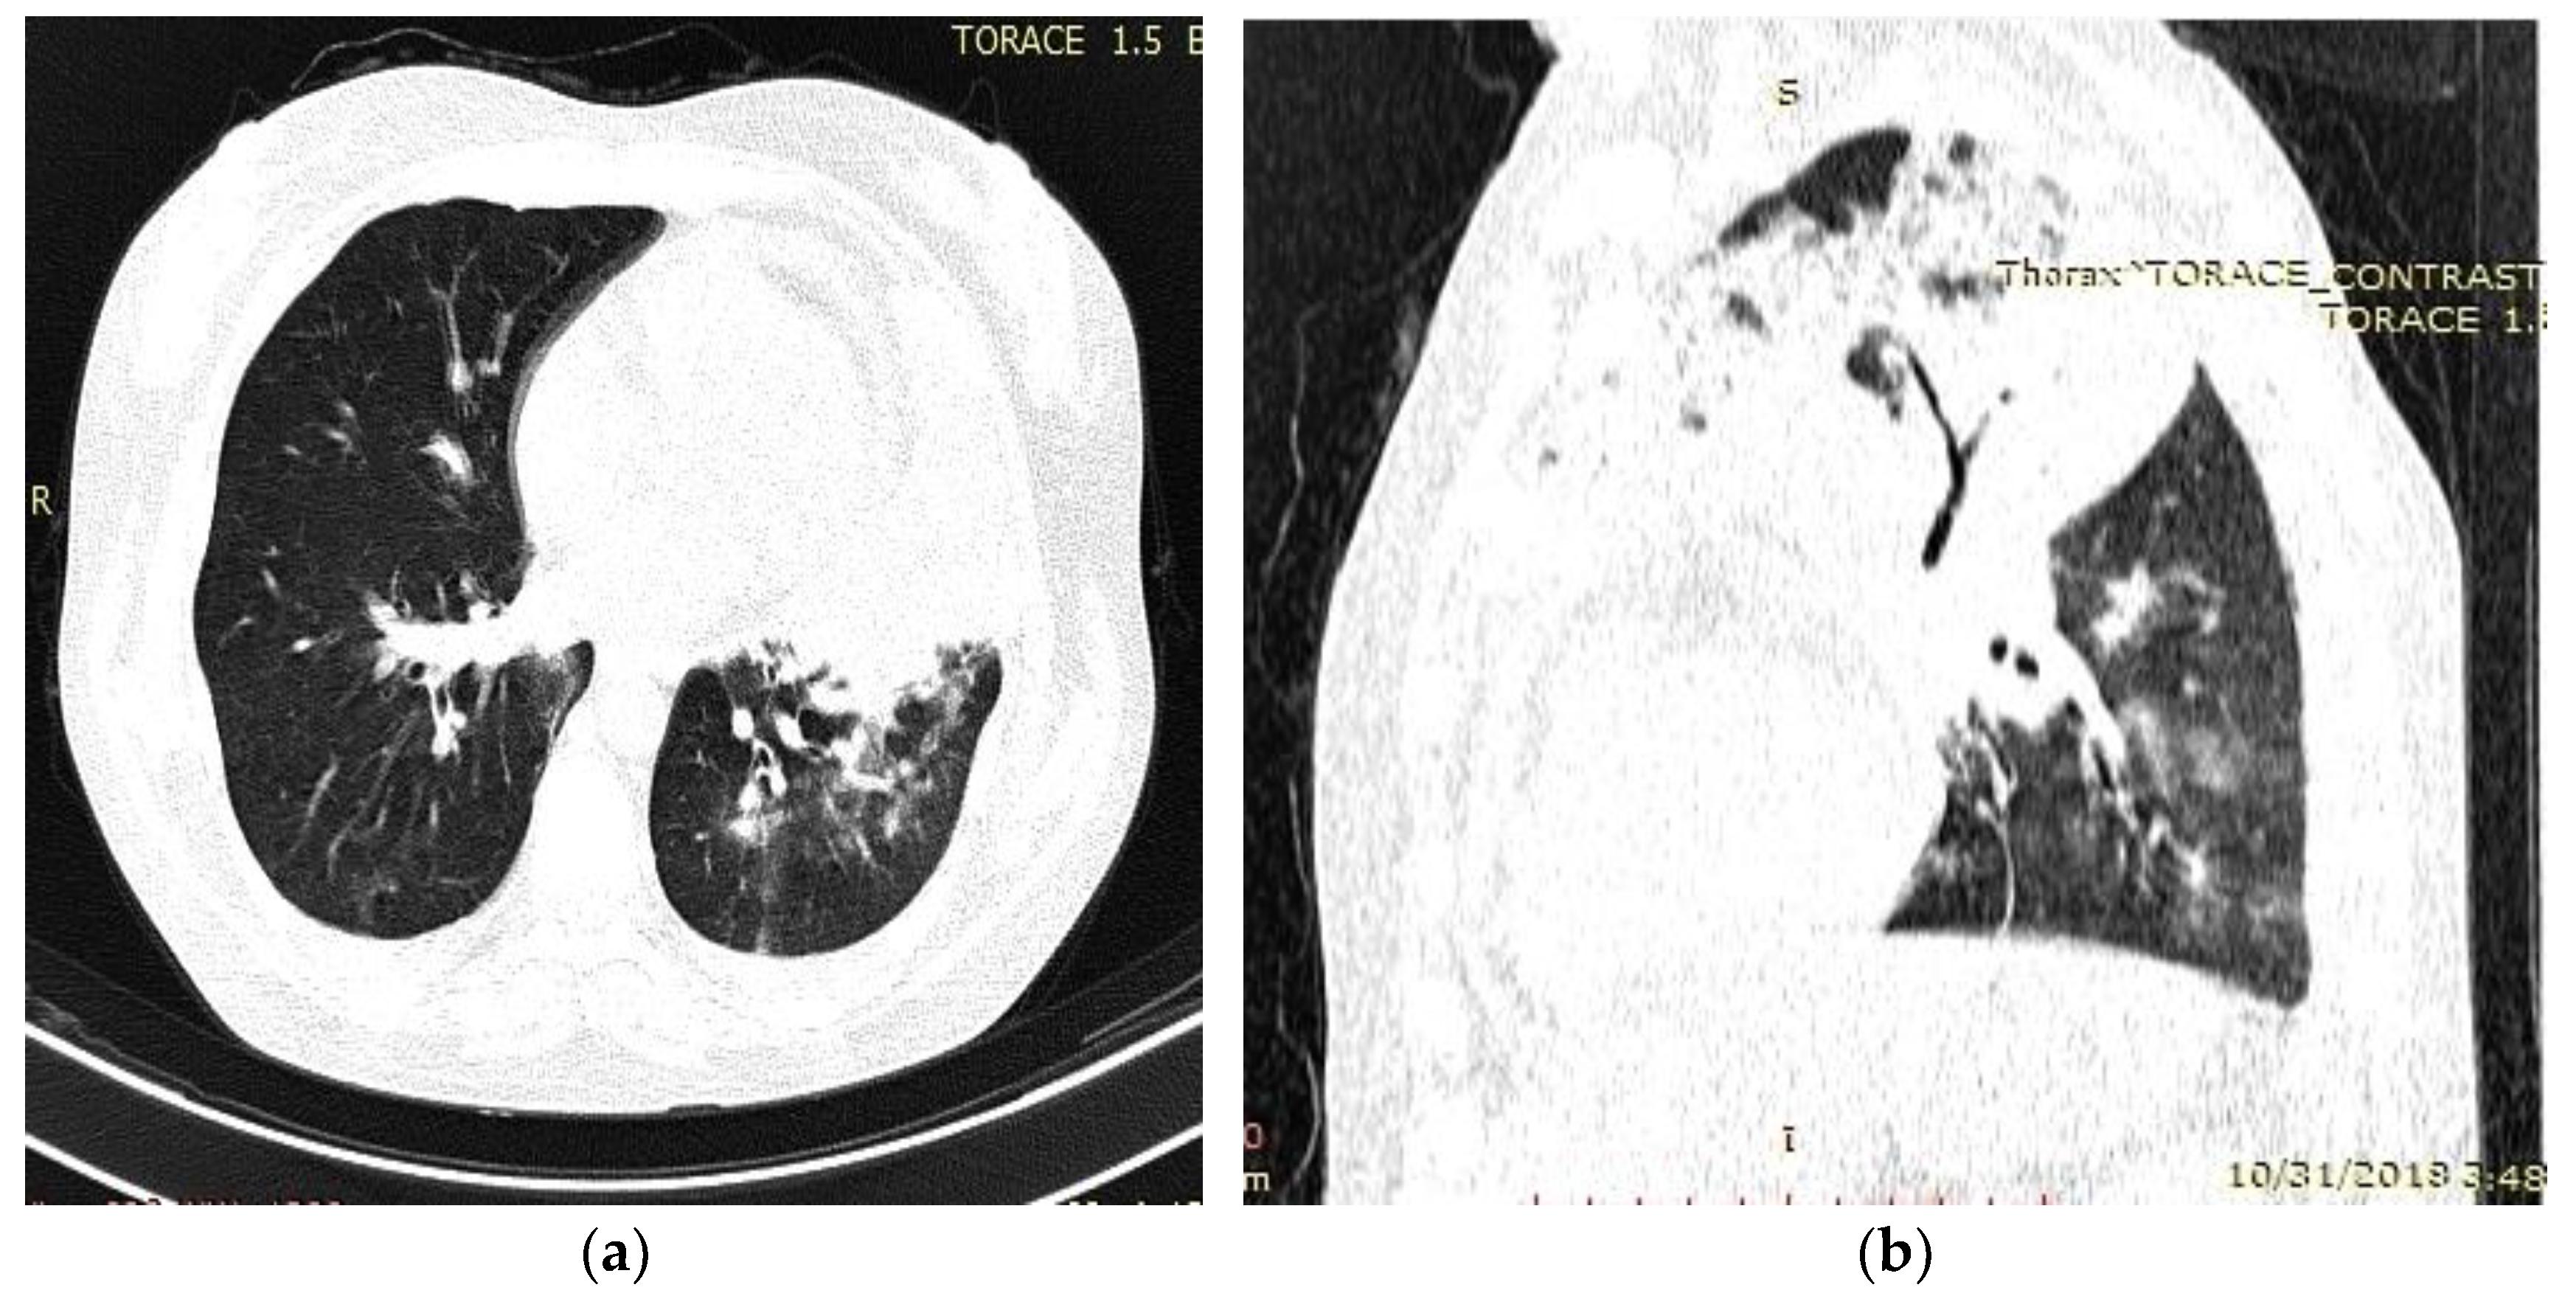

- Radiological evidence of chronic pulmonary lesion;

- Mycological demonstration of Aspergillus fumigates hyphae by microscopy from spu-tum, microscopy and culture from bronchial aspirate, and histopathological evi-dence of the presence of Aspergillus fumigates hyphae with dichotomous branching in the spinal cord biopsy;